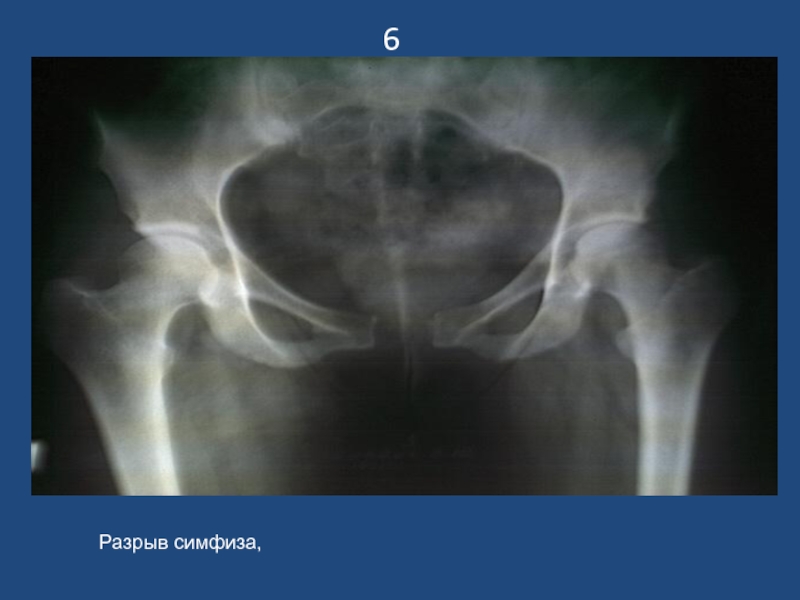

Слайд 76

Разрыв симфиза,